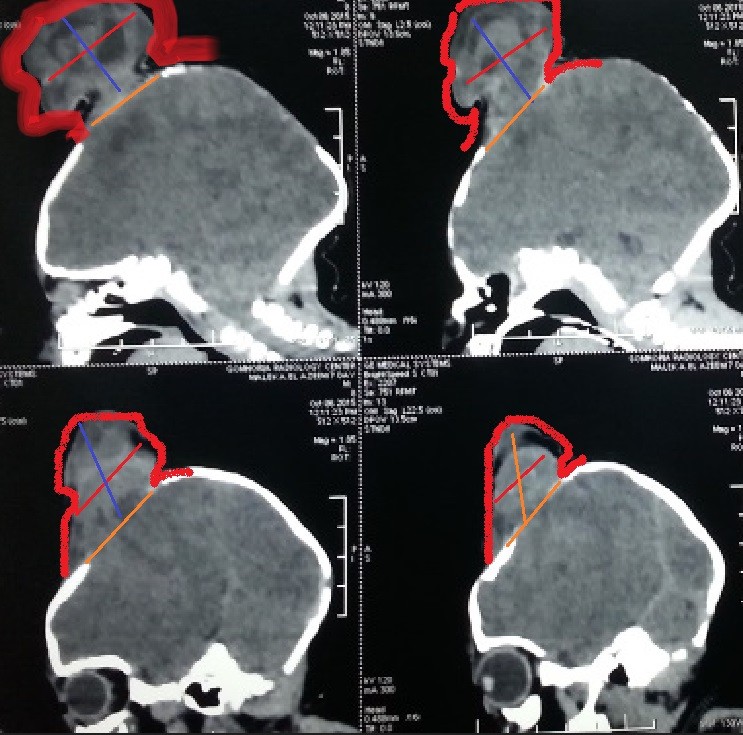

صور لحالة كاملة تم متابعتها منذ الأسبوع الأول من الولادة وحتي عمر ثلاث سنوات لطفل يعاني من قيلة مخية سحائية كبيرة .